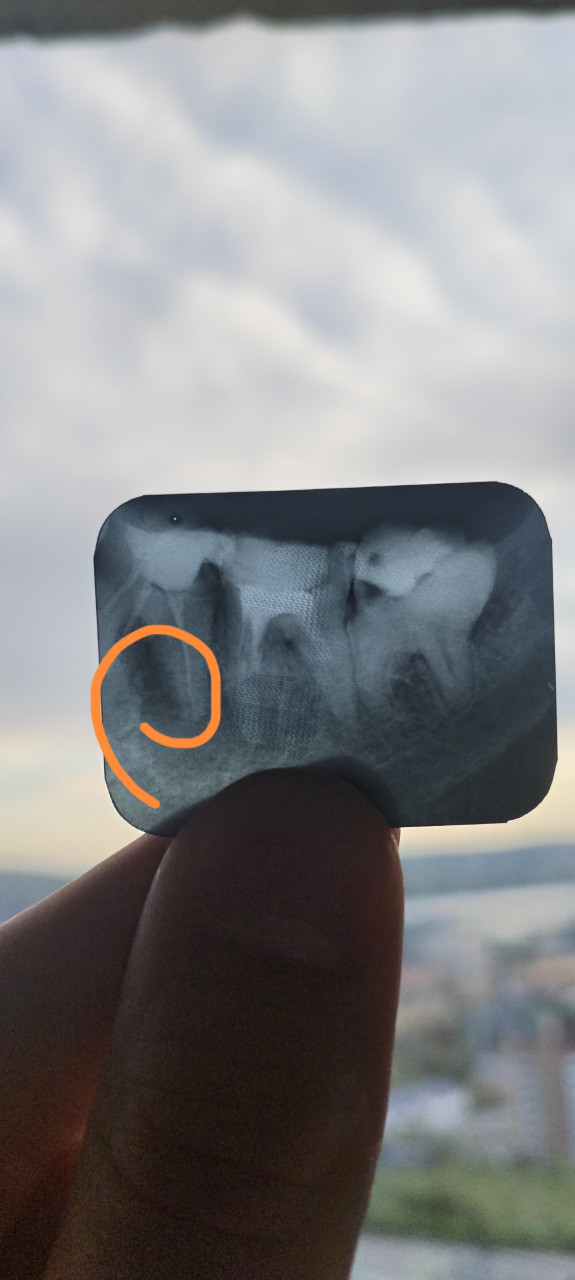

Здравствуйте! Можно ли удалить кисту зуба без удаления самого же зуба?

Здравствуйте! На снимке действительно видно образование в области корня похожее на кисту. Во многих случаях кисту можно удалить сохранив зуб в таком случае проводится операция (цистэктомия или гемисекция) при условии, что корень и окружающие ткани в хорошем состоянии. Решение принимает стоматолог-хирург после КТ и осмотра.